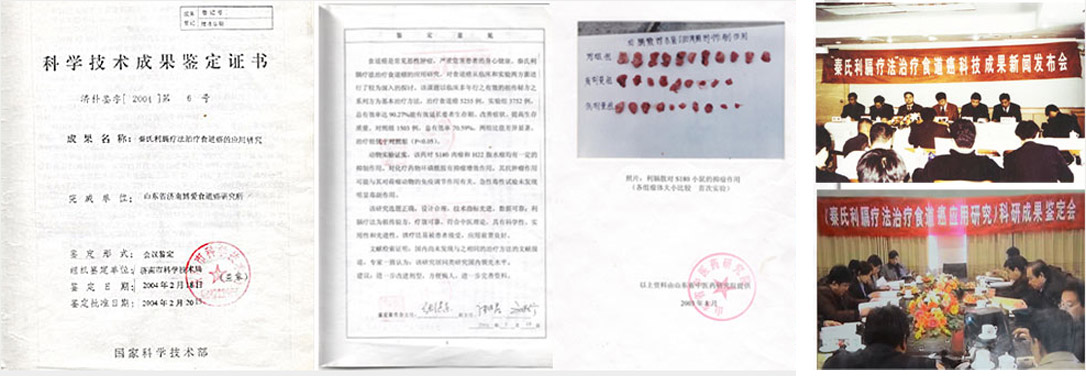

御医传承·百年验证良方